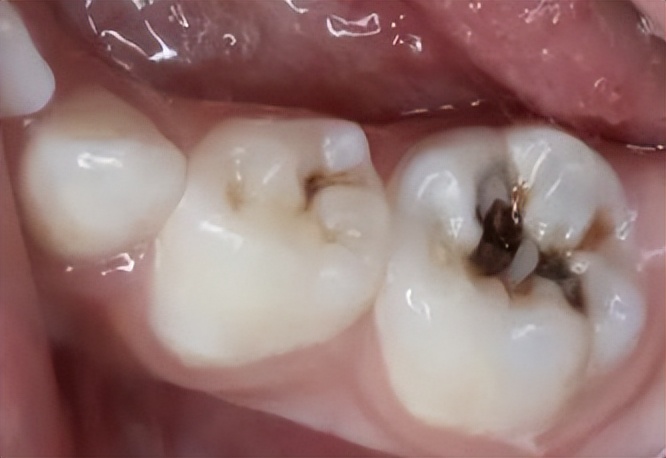

中龋

病变已达牙齿中层。临床检查可见牙齿表面出现窝洞,对外界刺激(如冷、热、甜、酸和食物嵌入等)可出现疼痛反应。

这个阶段吃苹果就有明显感觉了,嘎嘣脆的苹果一口咬下去,不但没有香甜,反而是又酸又软,一个苹果勉强吃完也是难受。